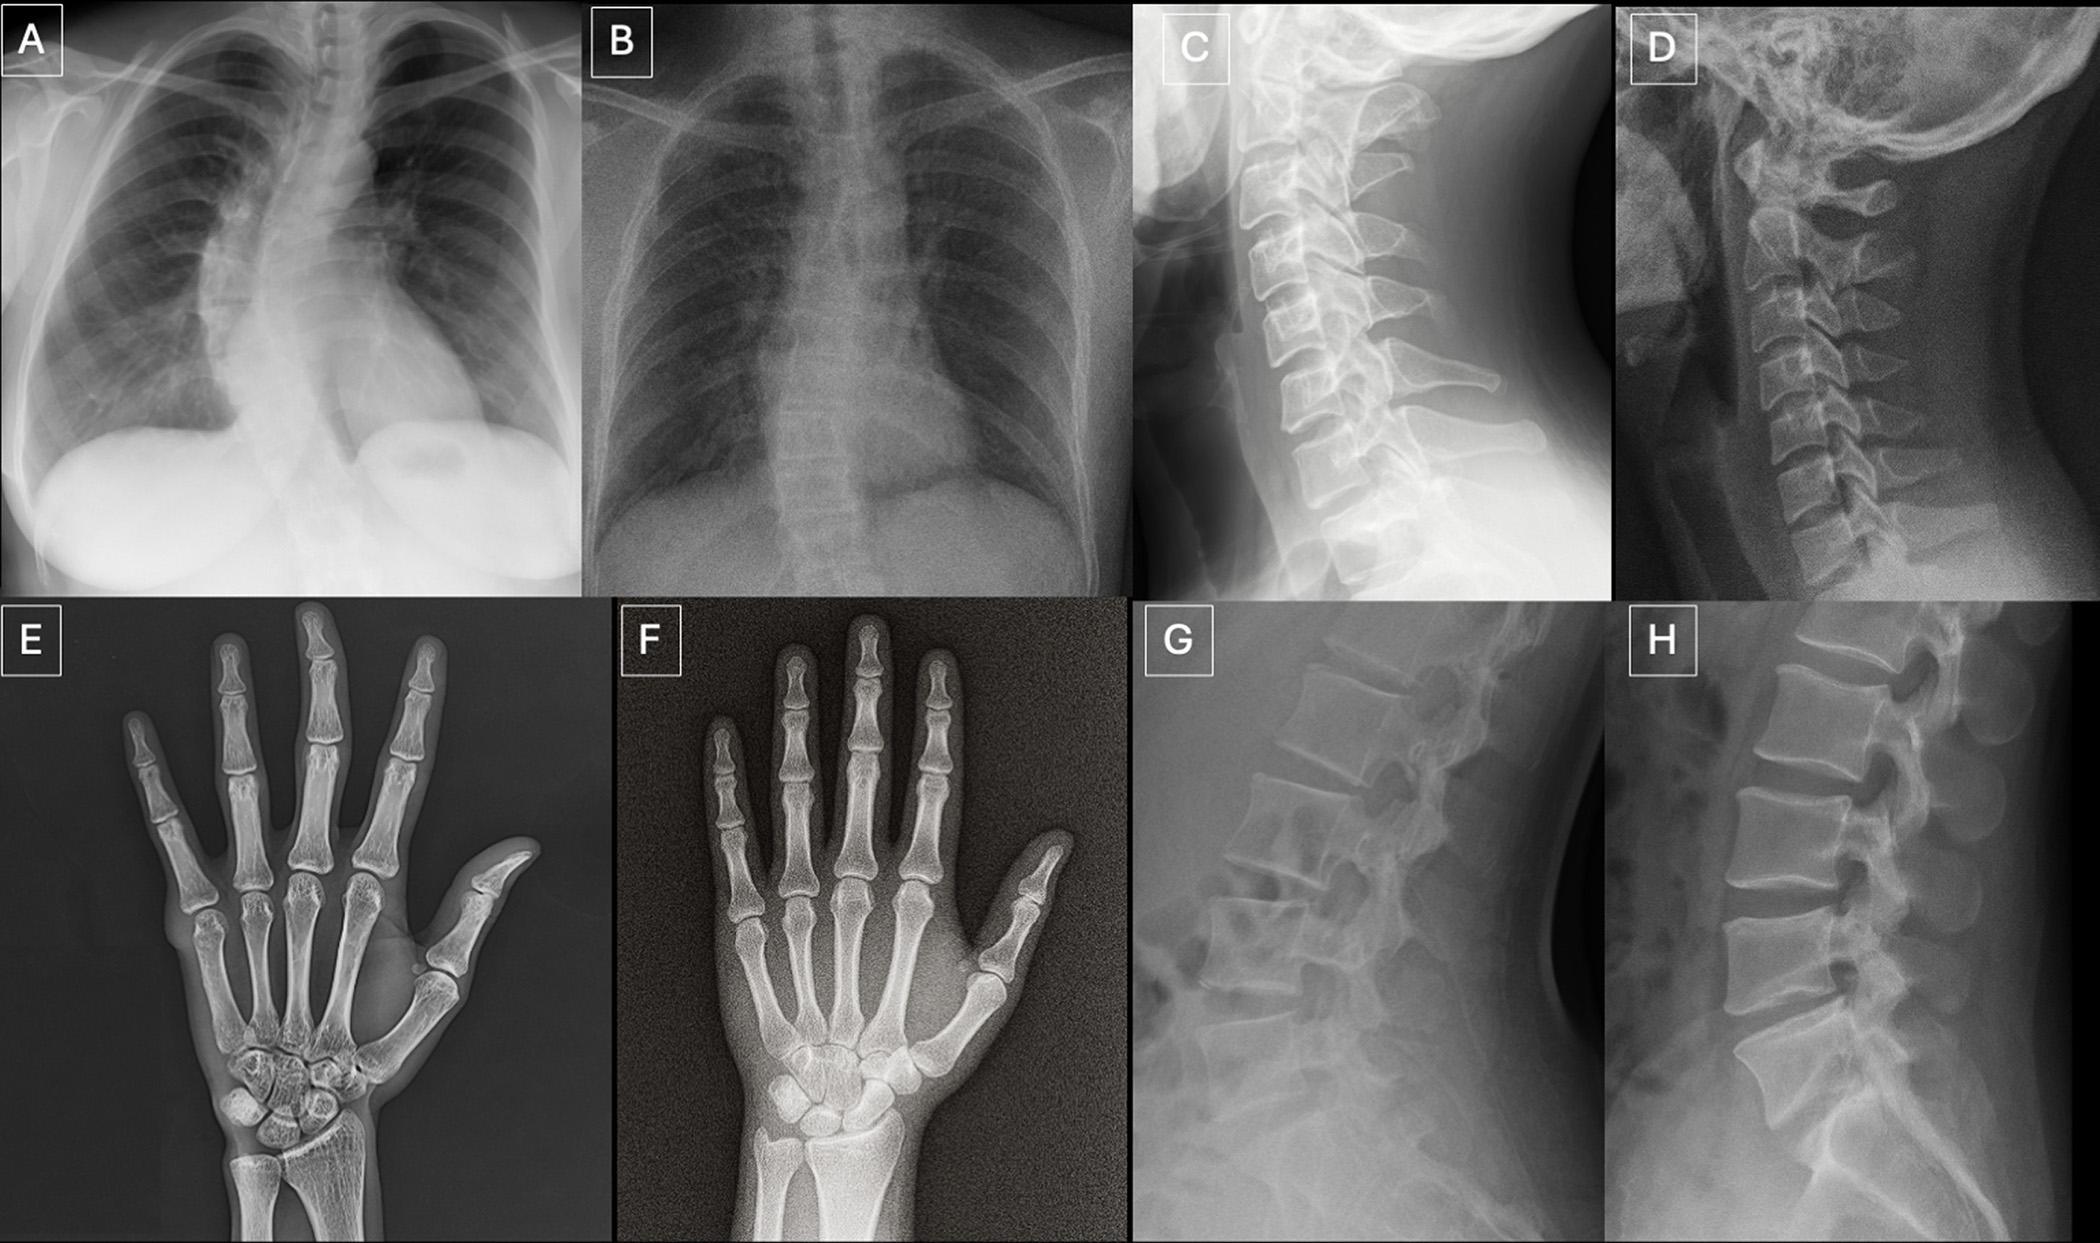

在这项回顾性研究中,来自美国、法国、德国、土耳其、英国和阿联酋6个国家12家医疗中心的17名放射科医生参与测试。研究共分析264张X光影像,分为两组:第一组数据包含多个解剖部位的真实影像以及由ChatGPT生成的影像;第二组数据为胸部X光片,其中一半为真实影像,另一半由斯坦福医学院研究人员开发的开源生成式AI扩散模型RoentGen生成。

研究人员总结称,AI生成的医学影像往往存在一些“过于完美”的特征,例如骨骼表面过于光滑、脊柱过直、肺部过度对称、血管分布过于均匀,以及骨折断面异常整齐等。